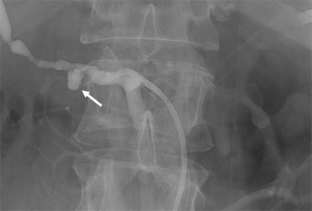

Fig. 2